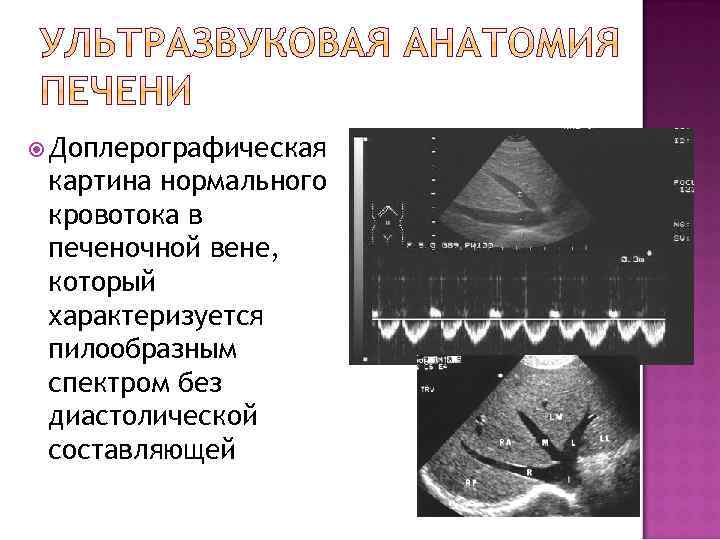

Доплерографическая картина нормального кровотока в печеночной вене, который характеризуется пилообразным спектром без диастолической составляющей